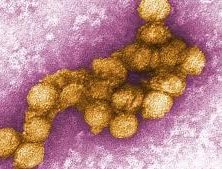

ウシ(牛)の病気  ウイルス

ウイルス  ウイルス

ウイルス  ウイルス